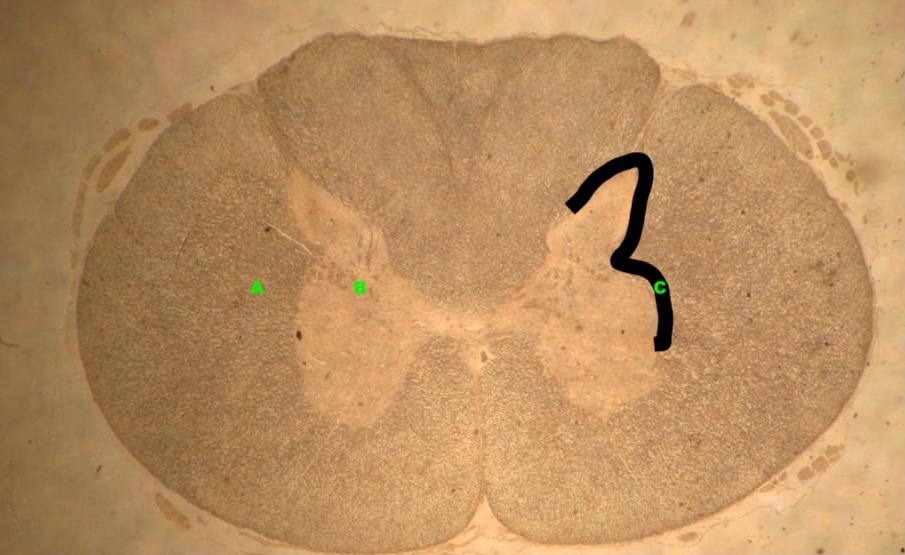

What is this and the structures labeled?

High or low power?

A

Spinal Cord at low power

A. White matter

B. Grey Matter

C. Greater wing